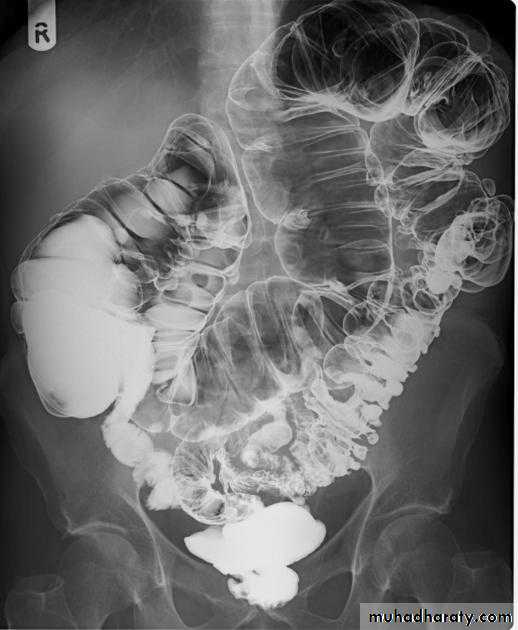

a. SB dilatation (mostly jejunal) in case of celiac disease

Celiac disease: The jejunum is devoid of most of its normal mucosal markings with Ileal loops in the pelvis have a prominent fold pattern

Celiac disease:

Flocculation and segmentation of barium indicate the presence of excessive fluid in the distal small bowel. The normal jejunal fold pattern also isabsent. These loops appear featureless. A few small bowel loops in the pelvis have thickened folds.